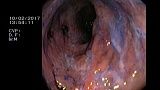

2 мл ( это мин сум, а мы делаем до 10 мл 3% перекись+200 мл физ раствора